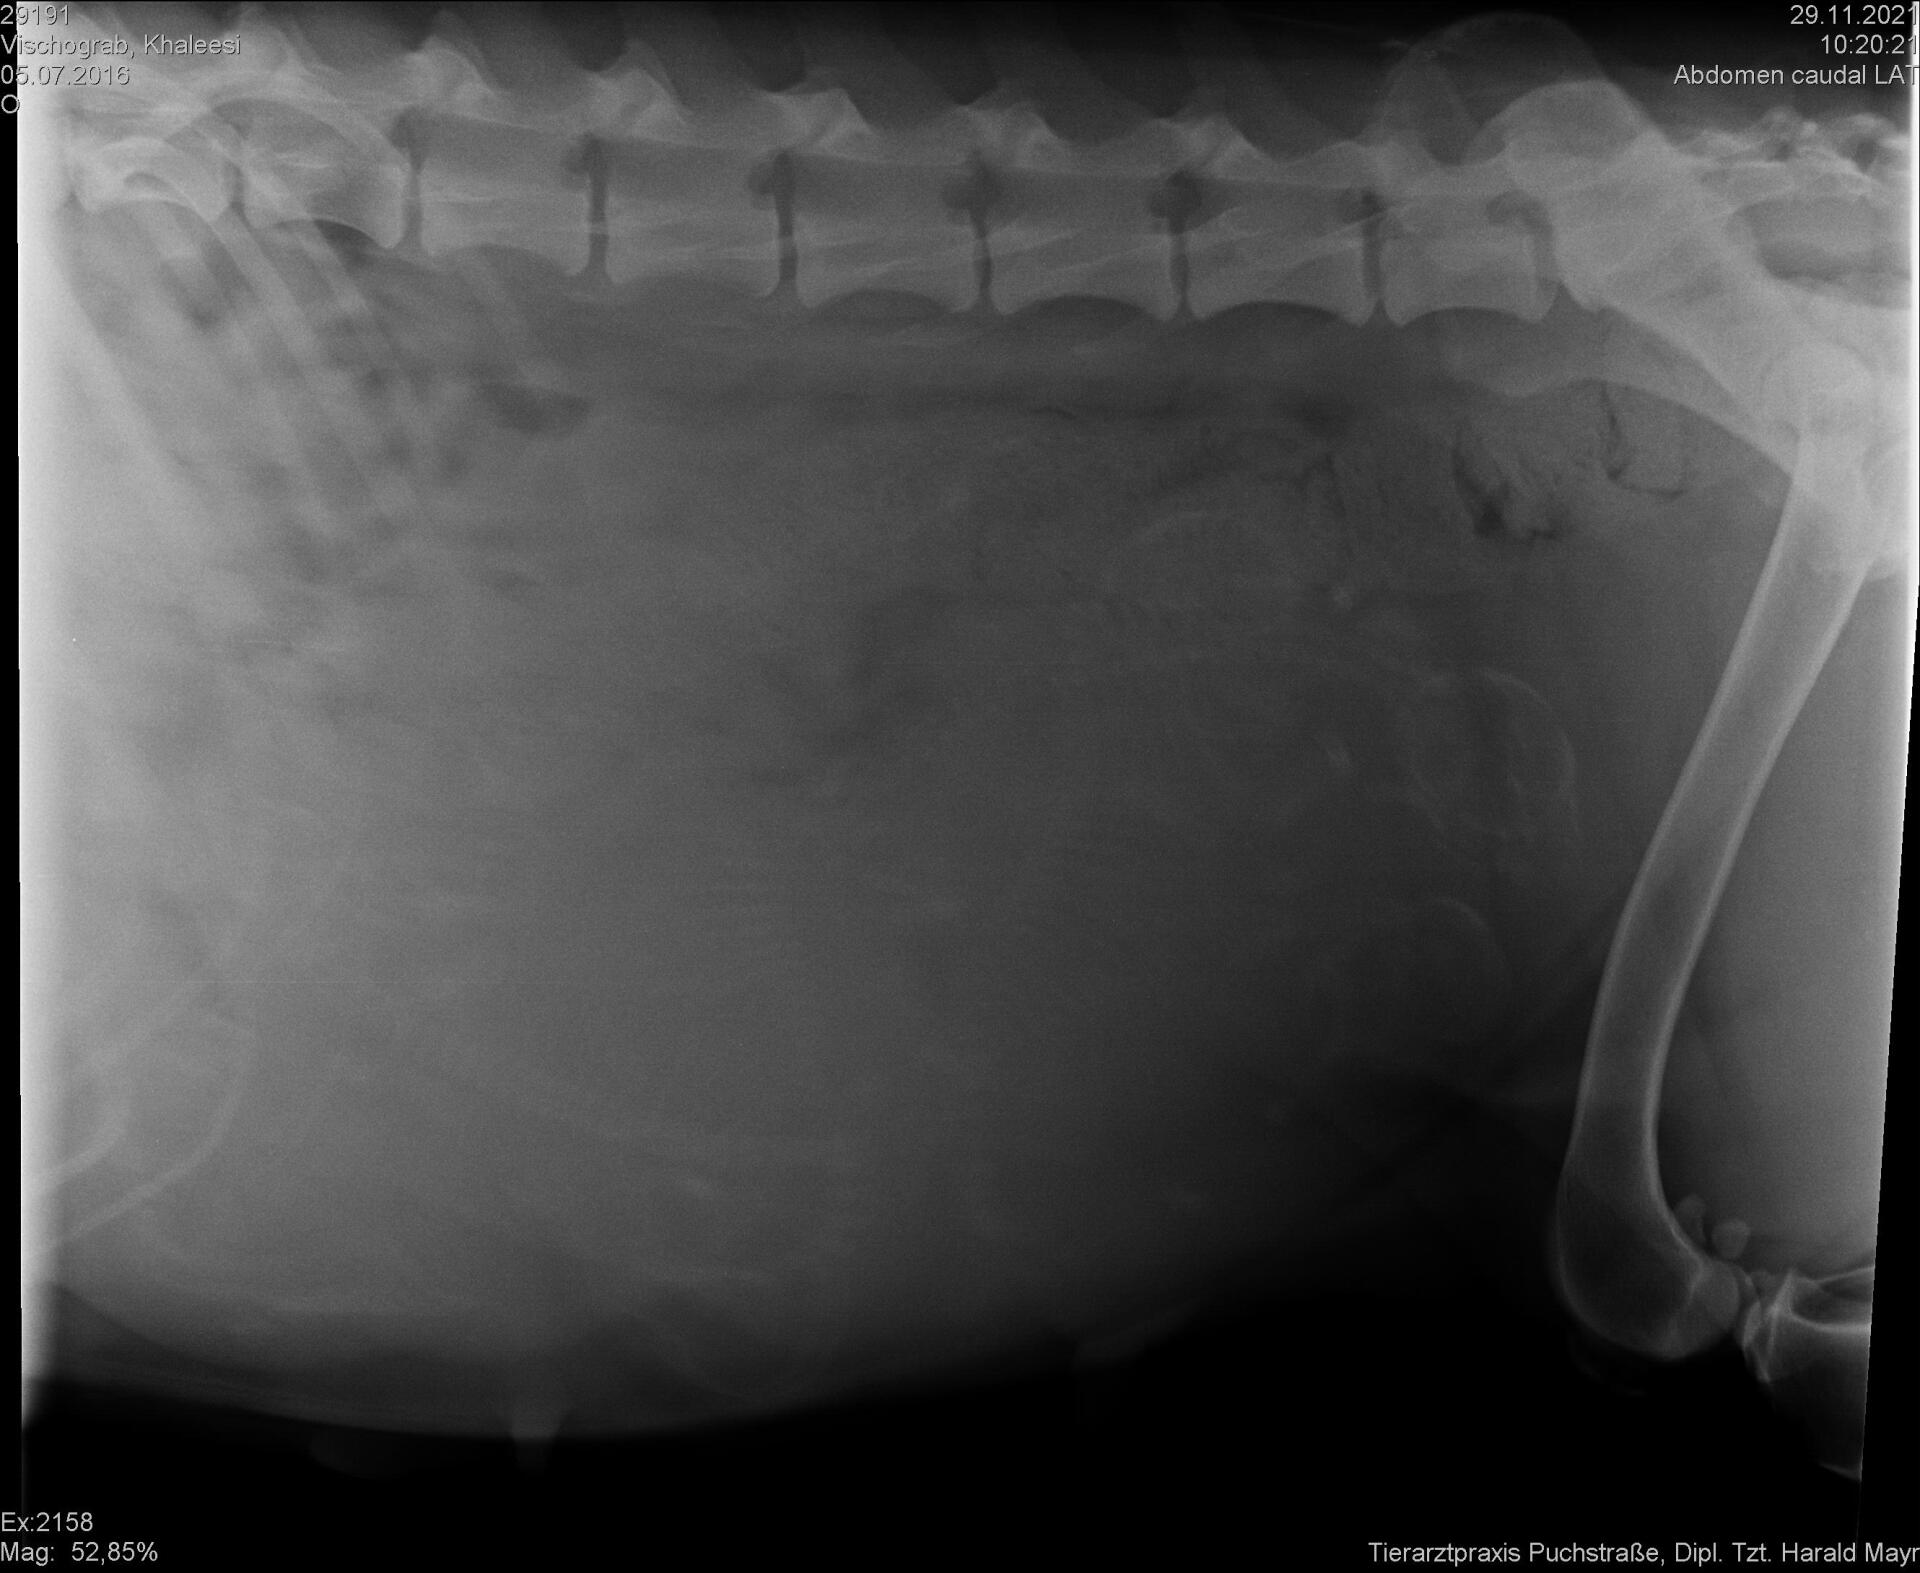

29.11.2021 - Röntgen

Heute haben wir ein Röntgen von unserer Khaleesi machen lassen um zu schauen wie viele Babys wir erwarten werden. Leider ist das Röntgenbild nicht sonderlich klar geworden, aber laut Tierärztin werden es zwischen 5 und 7 Babys werden! Jetzt geht es in den Endspurt. Die Wurfkiste steht schon, die Geburtsvorbereitungen laufen und wir zählen mittlerweile die Stunden bis zur Geburt!